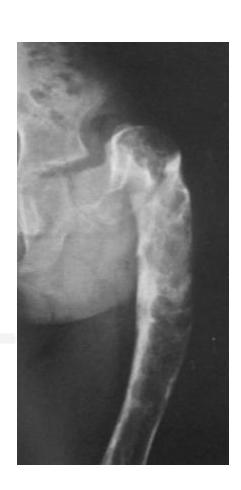

Osteosarcoma

Typical Presentation:

- Age: 10-20 years

- Pain and mass

- Location: Metaphysis of long bone

Characteristic Radiological Findings:

- Sunburst (Sunray) appearance

- Codmanโs triangle

- Periosteal reaction

- Bone eating appearance

Clinical Cases:

-

14-year-old patient with pain and swelling at lower right thigh

- Most important X-ray findings: Sun ray appearance, Codmanโs triangle

- Diagnosis: Osteosarcoma

14-year-old patient complaining of pain and swelling at lower R thigh

- Findings: Codmanโs triangle, Sun burst appearance